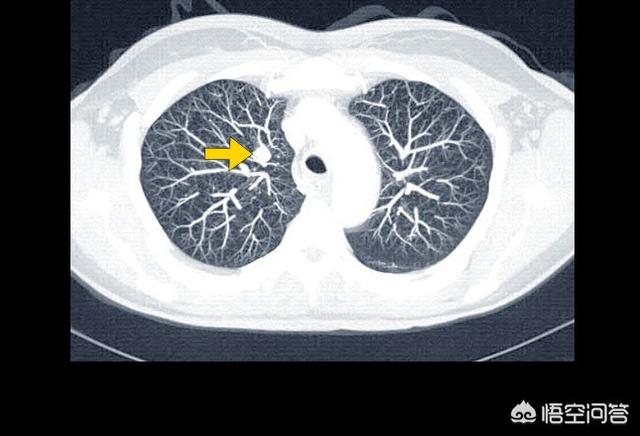

4.喀血と窒息 肺癌患者の多くは痰に血が混じる症状があり、特に中枢性肺癌の場合、腫瘍が太い血管に浸潤すると喀血が起こり、血液が気道に流れ込んで窒息し、生命が危険にさらされることがある。

第二に、喀血は窒息死につながるが、これもわかりやすい。喀血が突然起こると、呼吸が妨げられて救えなくなり、あっという間に死に至るからだ。

3.多量の吐血

肺がん患者が激しく咳き込むと、腫瘍と小動脈の癒着が破れて気管支が破裂し、大量の血液を吐き出して気道をふさぎ、窒息死に至ることがある。

(2) 喀血

また、肺がんが血管を侵し、強く咳をした後に血管が破裂して出血し、気道を塞いで窒息死したり、出血性ショックを起こしたりすることもよくある理由です。当院でも肺癌の進行期の医師が喀血し、病院全体で積極的な蘇生を行っても助からなかったことがあり、非常に残念でした。

3.窒息またはショックを引き起こす喀血:腫瘍がガスの通り道を塞ぎ、気管支壁を刺激し、気管が異物を排出しようとするため、咳が生じ、時に痰に血が混じる喀血となる。腫瘍が太い血管に浸潤すると、血管が破裂して喀血することがあり、劇症に血流が流れ込むと窒息やショック状態に陥り、生命を脅かす。一般に、患者が喀血症状を呈した場合は、病気が進行していることを意味する。